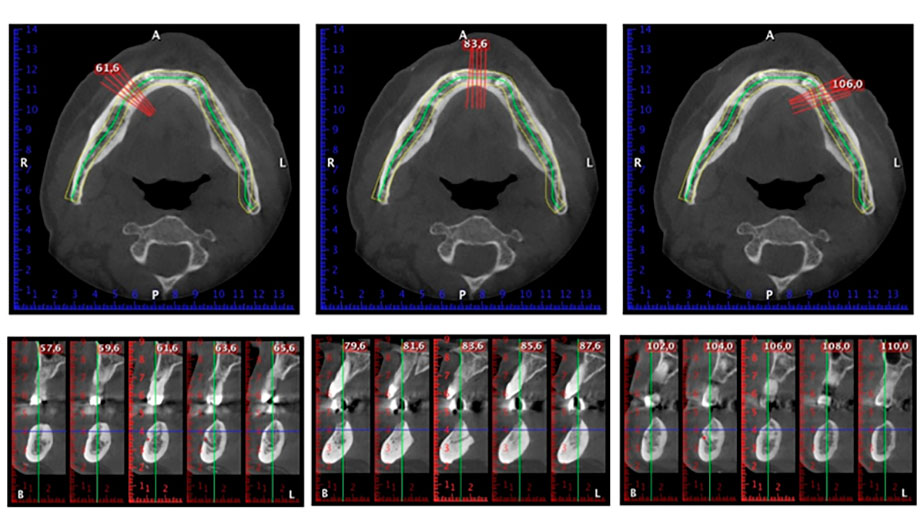

Un CT Scan à faisceaux coniques tridimensionnel (CBCT, Planmeca) a été réalisé au préalable afin de réduire les risques. Il a révélé une qualité et une quantité d'os disponible suffisante pour l'intervention chirurgicale et la restauration immédiate par la méthode All-on-four. En suivant le protocole de ce concept, les implants sont insérés au niveau de 35, 32, 42 et 45 en inclinant les implants distaux jusqu'à 45°, le profil d'émergence se déplace ainsi vers l'arrière et produit un polygone de stabilisation plus large (Fig. 3).

Méthode Fast & Fixed

Fig. 3